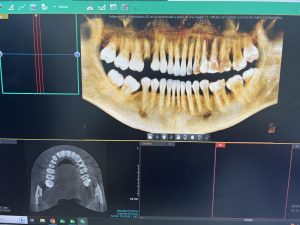

- Equipo Radiográfico para Radiografías Panorámicas y Escáner 3D